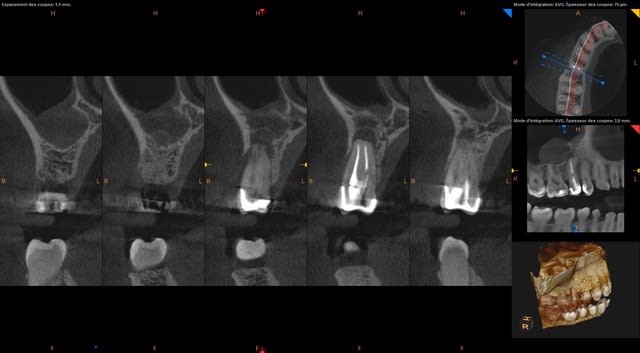

Je vous donne quelques images du cas. C'est pour un comblement per-extraction et eviter une CBS.

Screenshot 1.2.250.1.90.3.1251123212.20151007181521.5252 - Eugenol

Vu le scan il va être quasiment impossible de cureter efficacement, et donc greffer ici est très risqué.